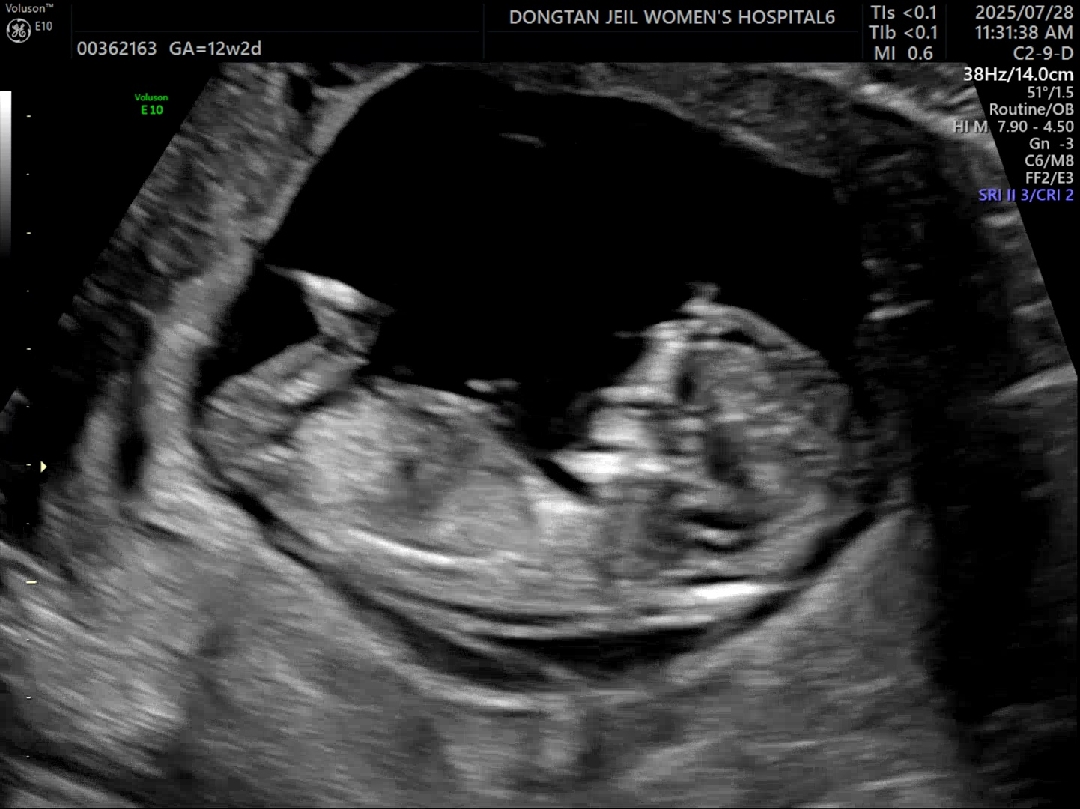

12주 3일차 1차기형아때 찍은 사진이에요!

이건 다리사진이요!